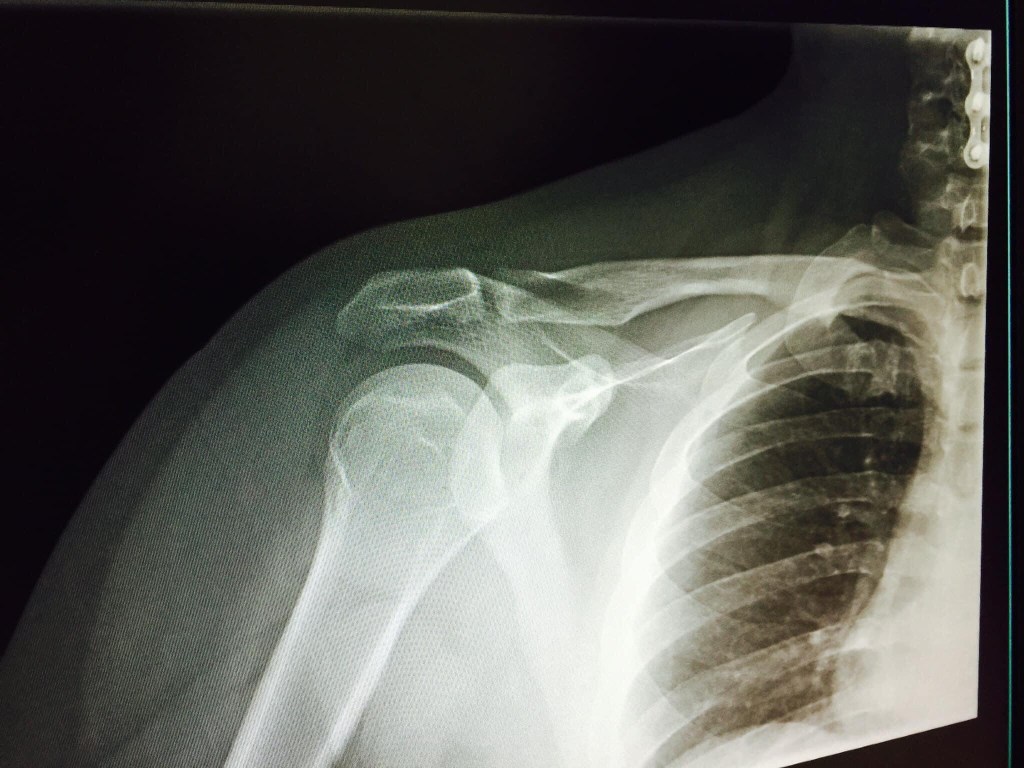

By the way I’m still sober and yeah did attempt suicide 3x’s but now, with 3 girls a Boy, a Wife and a Better life ahead That’s never gonna be on my radar ever again! Choices made also lead to lessons learned. For the Record, Pot, bongs, vape towers, bowls, joints and Dabs never made me “crazy”! Pain Did! Pretty Awesome Fact, I got more Medal in my Body than in my ShadowBox. Although it would be cool to have more Gold like the AFRAS Gold Medal I got.